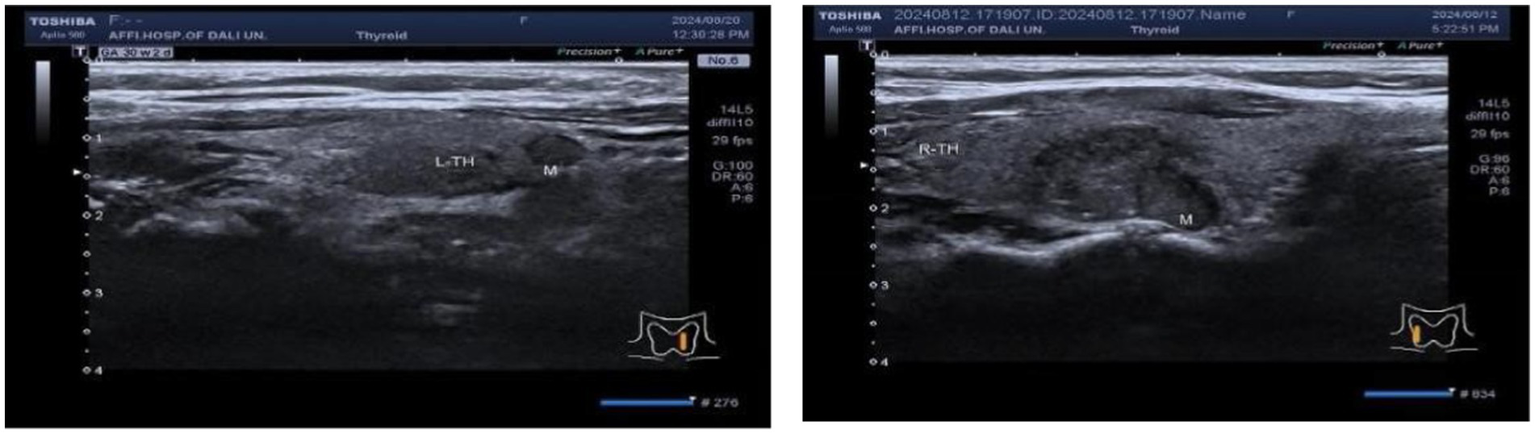

The correlation between ultrasonic characteristics of C-TIRADS and anxiety states needs to be further investigated

In a cohort of 303 patients, the HAMA results indicated that 126 patients exhibited normal anxiety levels, while 177 patients showed abnormal anxiety levels. Specifically, the HAMA results were categorized as follows: 126 patients without anxiety symptoms, 97 with possible anxiety, 47 with definite anxiety, 22 with definite and obvious anxiety, and 11 with possible severe anxiety. An ordinal logistic regression analysis was conducted to assess the impact of anxiety factors on c-tirads classification. These findings suggest that the presence of an unsmooth edge of TN is a risk factor for anxiety in patients, whereas protrusion outside the capsule is an influencing factor [p = 0.037, 0.028; B = 5.892, −5.723; OR, 95% CI: 362.080 (1.408–93142.282), 0.003 (0–0.054), Figures 4–7].

Figure 6

Ultrasound image of nodular lesion in the left lobe of the thyroid gland, C-TIRADS classification: 4B class, TN edge smooth, ultrasound image of nodular lesion in the right lobe of the thyroid gland, C-TIRADS classification: 4C class, TN edge not smooth.